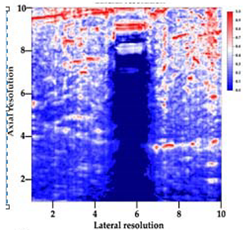

3.3. B-Mode Images

3.5. Echogenicity

4.1. Ultrasonography and Aerogel Dimensional Analyis

| Aerogel Type | US Image | Normalized Intensity Map | 3D Intensity Map | |

|---|---|---|---|---|

| 1 | Muscle |  |  |  |

| 2 | X-silica |  |  |  |

| 3 | X-silica-La2O2S:Eu |  |  |  |

| 4 | SMPU-Mix-14 |  |  |  |

| 5 | SMPU-Mix-18 |  |  |  |

| 6 | BRF-CA |  |  |  |

| 7 | ARF-CA |  |  |  |

| 8 | X-Ca-Alg-2 |  |  |  |

| 9 | X-Ca-Alg-1 |  |  |  |